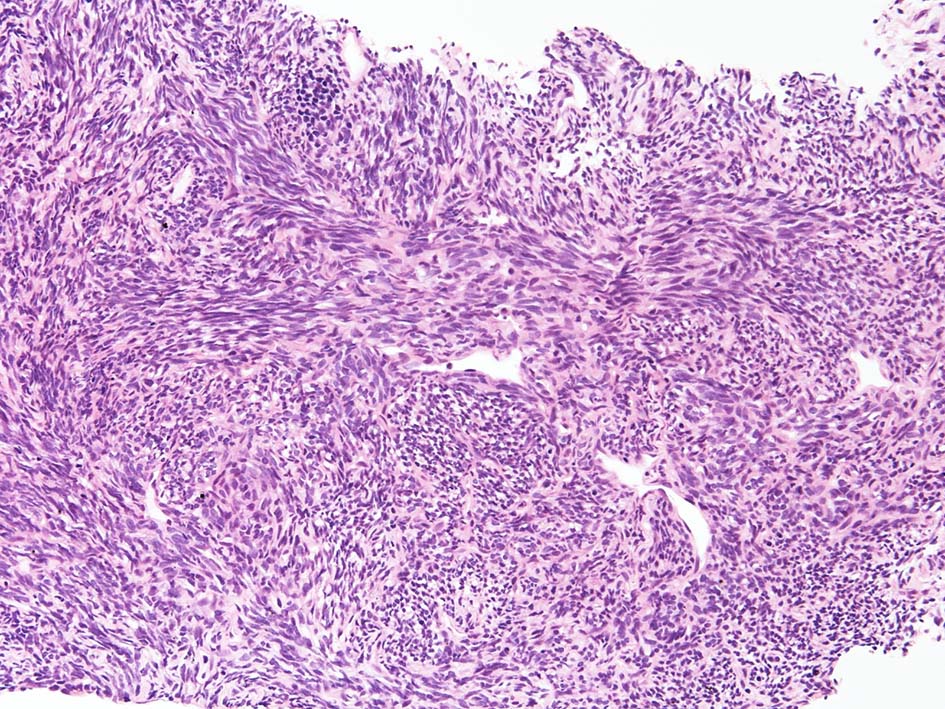

組織型

1. biphagic type; 古典的なタイプでさまざまな割合で明らかな上皮成分と紡錘細胞が混在する。

2. monophagic fibrous type; 線維肉腫様の紡錘細胞のみが増殖し上皮様細胞はみられない。

3. poorly differentiated type; 分化の低い類円形細胞肉腫でpericytomatous patternをとる。

biphasic type, monophasic typeは同じくらいの頻度で出現する。後者では免疫染色で上皮様分化をしめすこと, 特徴的な遺伝子異常を検出することが診断に必要となる。理論的にはmonophagic epithelial typeもあるが形態のみで診断は不可能。わずかな線維肉腫様成分をさがすことが診断にむすびつき, cytogenetic dataにより確診にいたる。